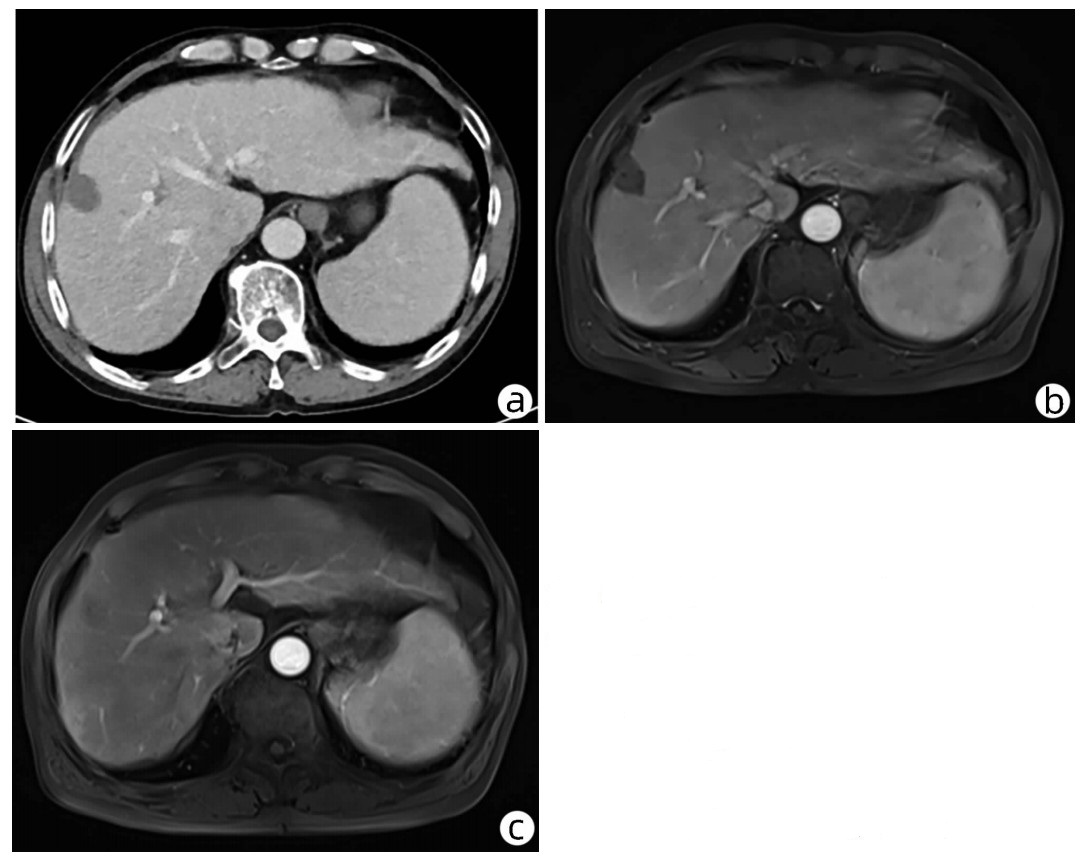

Late-onset diaphragmatic hernia after microwave ablation of hepatocellular carcinoma: A case report

Xiaodong WANG, Yurong ZHANG, Xiaoning ZHU, Ding ZHENG, Jing WANG

2022, 38(8): 1875-1877. DOI: 10.3969/j.issn.1001-5256.2022.08.029

Abstract(895) HTML (335) PDF (2572KB)(68)